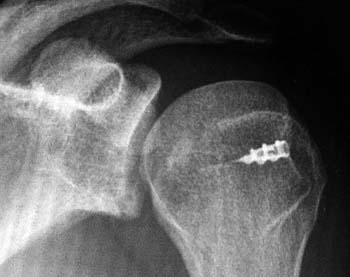

La resonancia magnética (RM) por su parte, permite evaluar ligamentos, tendones del manguito rotador y la lesión de Hill-Sachs, lo cual es de suma importancia a la hora de decidir el adecuado tratamiento (Fig. 1).

Figura 1: A: Radiografía en proyección AP con rotación interna. Se observa defecto Hill Sach. B: TAC de hombro, efecto posterolateral de la cabeza humeral .